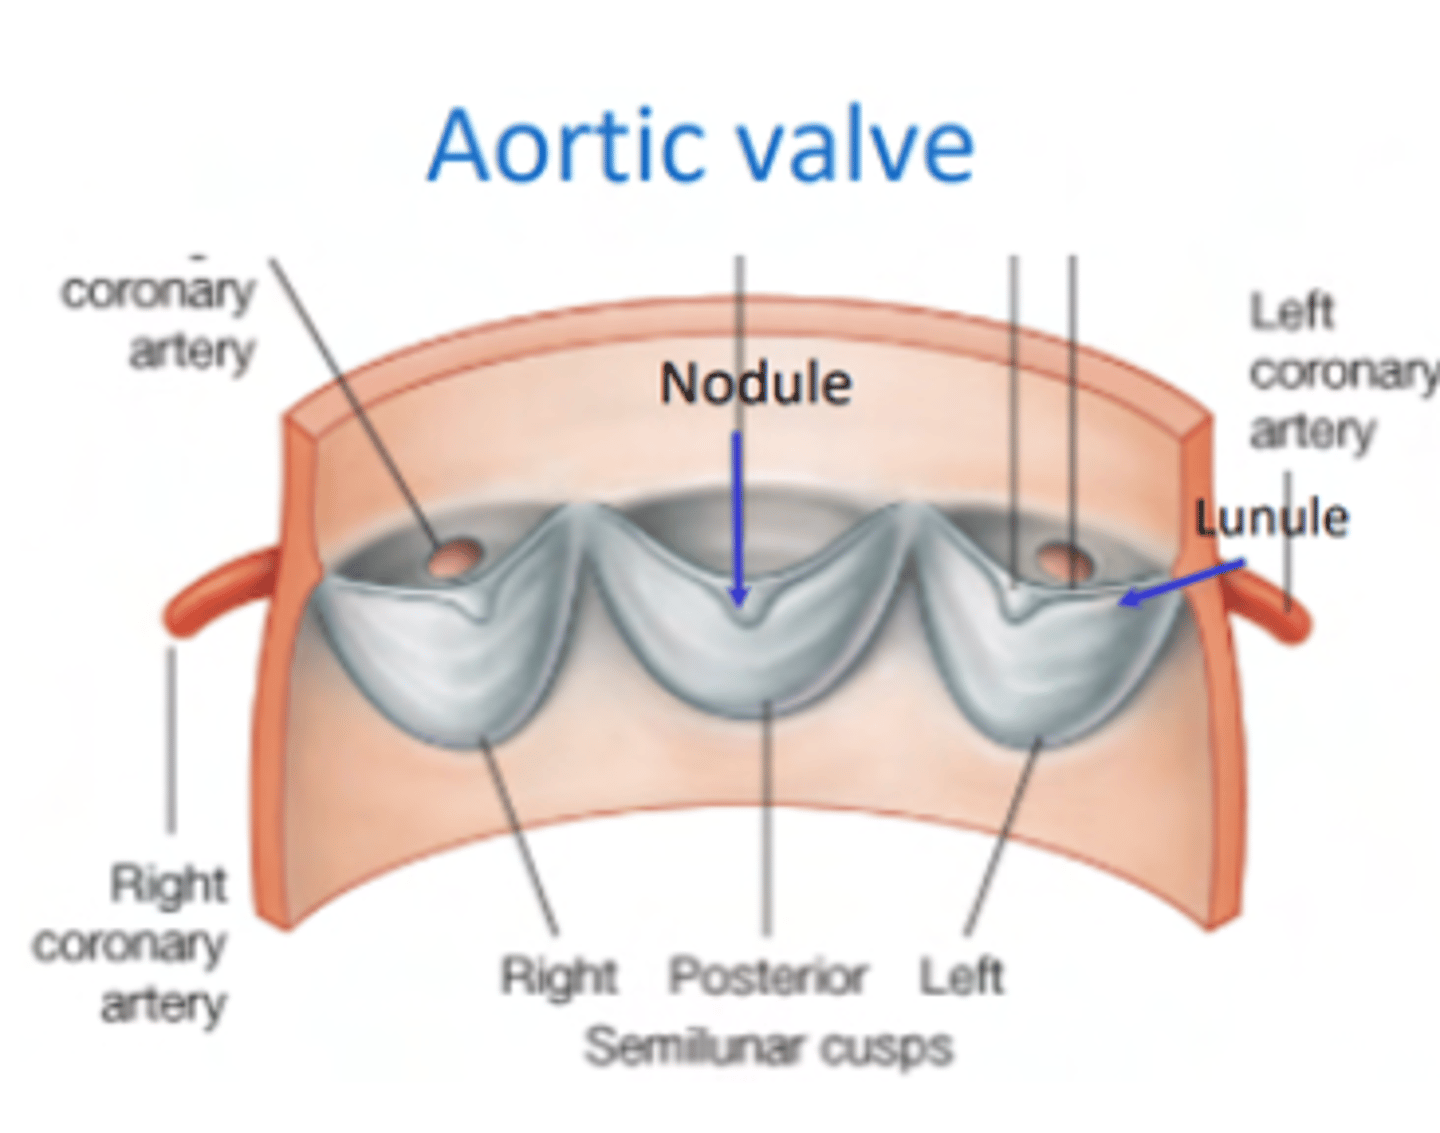

What is the valve to prevents reflux in the aorta?

Aortic valve

What are the 3 parts of the aortic valve?

3 semilunar cusps

posterior

right

left

POSITION IS DIFFERENT THAT IN THE PULMONARY (posterior vs anterior)

What is the structure of the cusps of the aortic valve?

. Nodules

. Lunules

. Small holes for the coronary arteries

MAIN DIFFERENCE WITH PULMONARY VALVES ARE THE SMALL HOLES FOR THE CORONARY ARTERIES.

What is the 1st branch of the aorta?

The small holes in the aortic valve cusps to irrigate the coronary arteries.